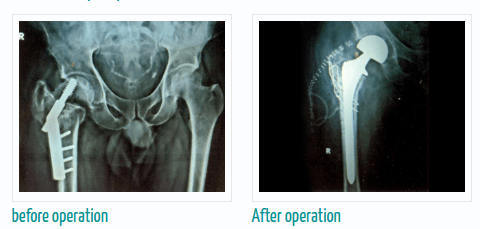

If you are thinking about getting arthroscopic surgery, consider seeing Dr. Murtaza Adeeb. He is a great doctor for joint replacement, and you can meet him at the Advanced Bone Care Clinic wanawadi Road Fatimanagar Pune.

Dr. Murtaza Adeeb is known for being really good at robotic knee, hip, and joint replacement surgery. To make an appointment with Dr. Murtaza Adeeb,